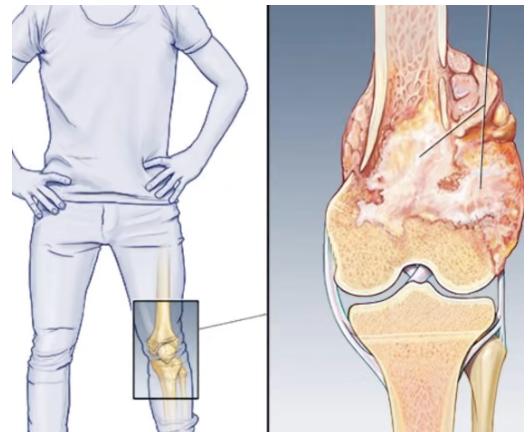

骨肉瘤是一種起源于間葉組織的惡性腫瘤,以能產(chǎn)生骨樣組織的惡性梭形基質(zhì)細(xì)胞為特征,又稱成骨肉瘤,是青少年最常見(jiàn)的原發(fā)惡性骨腫瘤,好發(fā)于四肢長(zhǎng)骨干骺端,其中一半以上的病例發(fā)生于膝關(guān)節(jié)周圍。它的出現(xiàn),就像一顆隱藏在身體里的定時(shí)炸彈,隨時(shí)可能給孩子的健康帶來(lái)嚴(yán)重威脅。

骨肉瘤的典型癥狀是疼痛和局部腫塊。早期疼痛多為持續(xù)性隱痛、鈍痛,很快就會(huì)發(fā)展為持續(xù)性劇痛,夜間疼痛更加明顯,且休息后難以緩解。隨著病情進(jìn)展,局部會(huì)出現(xiàn)腫塊,腫塊大小差別很大,表面皮膚溫度升高,淺靜脈充盈或怒張,部分患者還可能出現(xiàn)病理性骨折。此外,骨肉瘤還可能引發(fā)全身癥狀,如發(fā)熱、消瘦、貧血等。